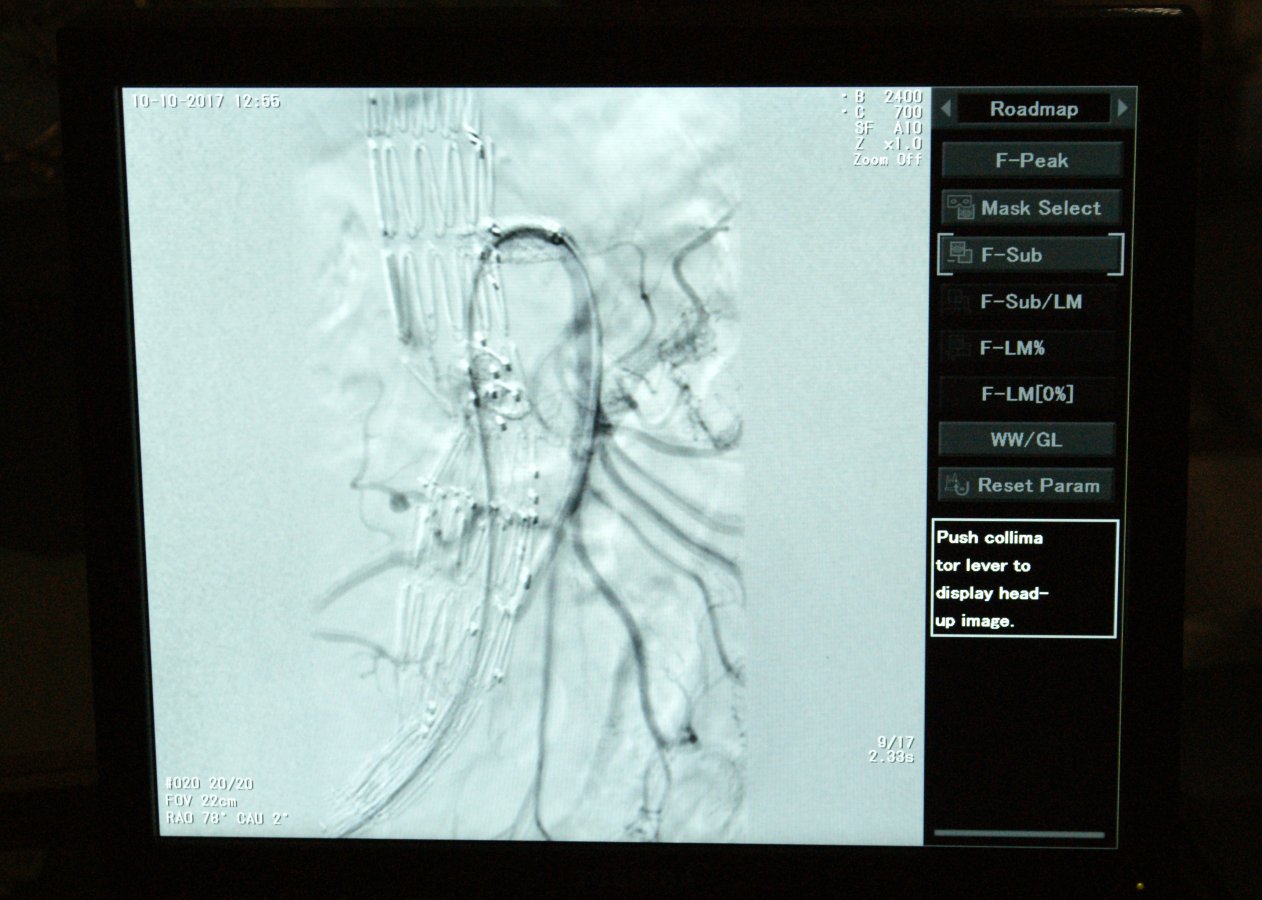

Teraz białostoccy lekarze rozpoczęli operowanie przez „dziurkę od klucza” - do aorty dostają się przez pięciocentymetrowe nacięcia w pachwinach. Wcześniej jednak do takiego zabiegu muszą się odpowiednio przygotować.

- Po zdiagnozowaniu tętniaka kierujemy pacjenta na angiografię CT, czyli tomografię komputerową naczyń krwionośnych - tłumaczy dr hab. Jerzy Głowiński, p.o. kierownika Kliniki Chirurgii Naczyń i Transplantacji w USK. - Wynik przesyłamy do firmy, która wytwarza indywidualnie dopasowane do każdego pacjenta stentgrafty, czyli protezy wewnątrznaczyniowe. Ten wynik jest obrabiany komputerowo, a następnie stentgraft jest szyty na miarę w Nowej Zelandii. Po sześciu tygodniach dostajemy gotowy, dopasowany anatomicznie dla danego pacjenta stentgraft fenestrowany, czyli taki, który ma specjalnie przygotowane otwory na odchodzące od aorty naczynia.

Jak mówi dr hab. Jerzy Głowiński ta precyzja jest bardzo ważna: każdy człowiek ma w innym miejscu odejścia tętnic nerkowych czy krezkowych i nawet jeden milimetr ma tu znaczenie.

Nowej metody operowania białostoccy lekarze uczą się od prof. Piotra Kasprzaka z Kliniki Chirurgii Naczyń Szpitala Uniwersyteckiego w Regensburgu. Prof. Kasprzak ma największe w Europie doświadczenie w tego typu operacjach: do tej pory przeprowadził i nadzorował ponad tysiąc takich operacji. Wspólnie wykonali już dwa zabiegi i dziś (11 października) planują wykonać kolejny trzeci. Kolejnych dwóch pacjentów białostoccy chirurdzy naczyniowi, dr hab. Jerzy Głowiński i dr Adam Płoński, planują samodzielnie zoperować do końca tego roku. Mają nadzieję, że tego typu zabiegi będą stale wykonywane w Białymstoku. Problemem jest bowiem cena stentgraftów. Do takiej operacji potrzebne są dwa stentgrafty „szyte na miarę” oraz 3-4 standardowe stentgrafty do naczyń trzewnych. Wszystko to kosztuje około 200 tys. zł.